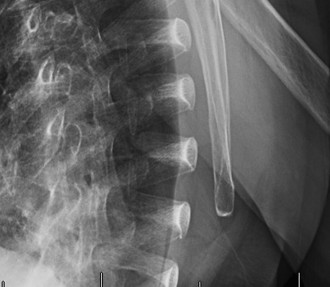

Rotator cuff tears are a common reason for shoulder pain and a common reason to obtain shoulder imaging. As a result, numerous different imaging modalities exist offering different pros and cons. Plain films are still the initial imaging modality of choice. These are most useful in ruling out other possible diagnosis but can help with the diagnosis of a rotator cuff tear as well. Changes to the tendon itself

may appear as calcific tendinosis, which would most commonly be seen at the bone–tendon interface. A decrease in the acromiohumeral distance (less than 2 mm) may also be indicative of a cuff tear. In late cases of rotator cuff tears, superior subluxation of the humerus may be evident. Certain variations in acromial anatomy, including spurs or a hook-shaped (type 3) acromions, may be associated with rotator cuff tears as well. With progression of rotator cuff tears, degenerative changes including spurs, cysts, and sclerosis may be evident at the greater tuberosity. In late, massive tears one may see degenerative changes consistent with rotator cuff arthropathy.